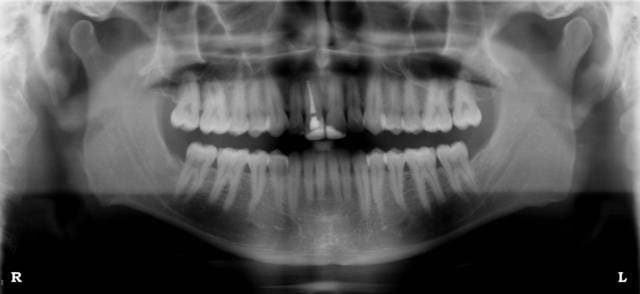

Cet appareil est visible et essayable dans l'est et dans l'ouest de Paris.

Clichés dispos en pièce jointe.

dis JAOUI , il est drolement bien le bloc antérieur sur ta panoramique sans filtre , mais dis-moi , tu l'a prise avec ou sans flach ...